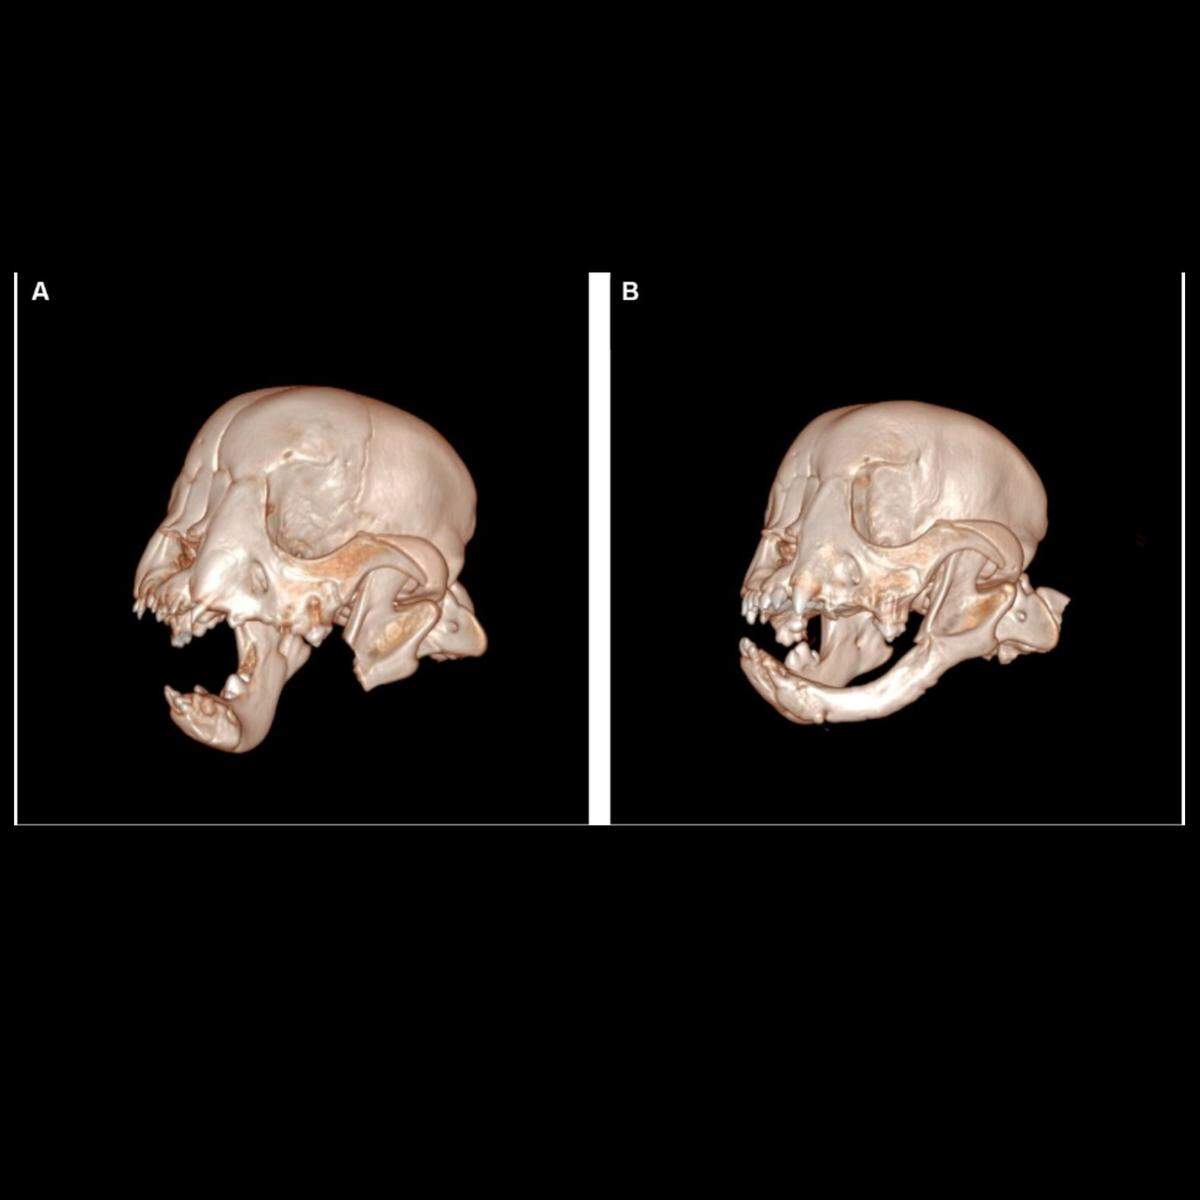

The team took a CT scan of his head and found new bone had grown where a hole had been left, according to the case report.

The bone wasn’t entirely the same, the veterinarians said in the case report. There was no mandibular canal, a channel holding major blood vessels, and no teeth, but the length of the bone on the left now matched the right, preventing the jaw from drifting, the veterinarians said.

“In humans, young patients who undergo mandibulectomy have been reported to regenerate new bone,” the veterinarians said in the case report. “This is the first report of spontaneous regeneration of the mandible following oral oncological surgery in a dog.”